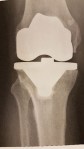

Jetzt habe ich es bereits hinter mir. Am 19.10.2017 wurde mein kaputtes, pardon „komplex beschädigtes“, linkes Knie repariert. Genauer gesagt wurde eine Knie- Prothese eingesetzt. Der Eingriff verlief problemlos und am 20.10.2017 könnte ich mein Knie bereits wieder leicht belasten und biegen. Am 22.10.2017 habe ich mit der REHA begonnen. Ab Morgen bin ich bereits wieder zu Hause. Eine stationäre REHA ist nicht nötig da mein Fitnessstand gut ist und ich diese in meinem vertrauten Umfeld von zu Hause aus absolvieren kann. Der Vorteil einer guten Wohnlage mit allem drum herum…